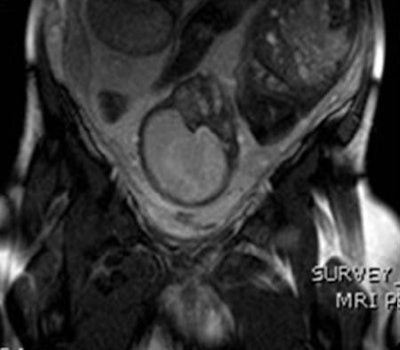

Abnormal placenta was revealed in 21 cases: four cases of acreta, 11 cases of increta, and six cases of percreta. In one case, the presence of fibromas complicated sonographic appearances and was clarified by MRI.

There was surgical confirmation of MRI findings in 10 of the 21 cases; in five cases that MRI had suggested wall and bladder penetration, surgical findings did not concur. In two cases, MRI findings suggested subtle uterine rupture, which was confirmed intraoperatively.